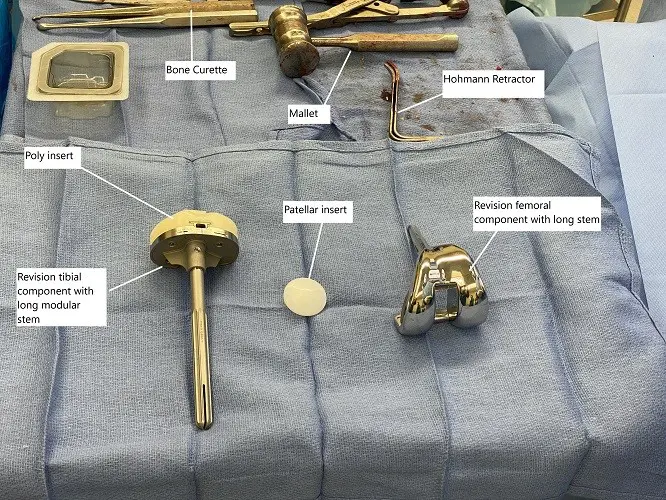

A loose femoral component is managed with a revision involving a femoral component with a long stem. Rarely, an extensive fracture in the elderly may require the replacement of the entire lower end of the femur (distal femoral replacement).

Tibial fractures occur most commonly due to mal-aligned components or in patients with a prior history of tibial surgery. Nonsurgical treatment in the form of bracing/casting may be done for nondisplaced stable fracture. Unstable fractures with a stable prosthesis may be managed with plates, cables, wires, etc. Fractures with an unstable prosthesis are revised usually with a long stem prosthesis.

Intraoperative implants and instruments used in revision knee surgery.

Patellar fractures leading to disruption of the extensor mechanism (the ability to raise a straight leg), or with an unstable prosthesis are managed with surgical treatment. The surgical treatment may consist of removal of the patella, wire fixation, partial removal of the patella, revision of prosthesis, etc.

- Revision Surgery: If the implant is loose or misaligned, revision surgery may be required to replace or reposition the prosthetic components. In some cases, long stem prostheses may be used for better fixation.

- Patellar Fracture Surgery: In cases of patellar fractures, surgery may involve removing damaged fragments, using screws for fixation, or revising the patellar component.